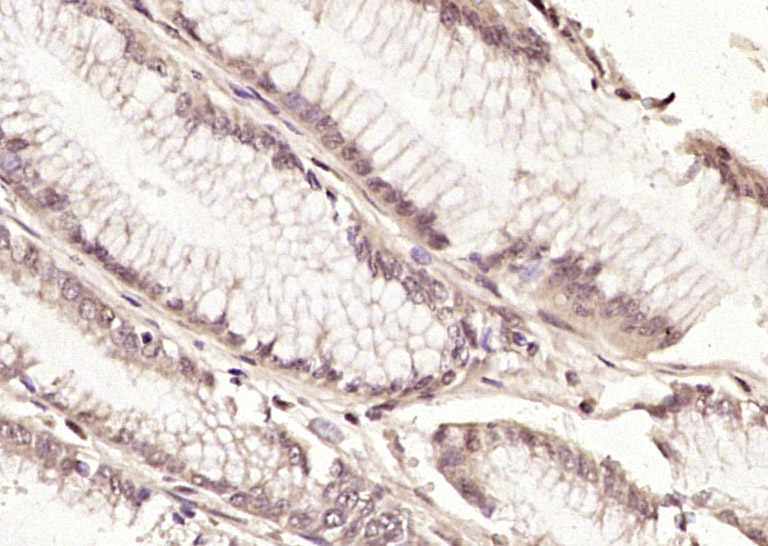

| 产品应用 | WB=1:500-2000, IHC-P=1:100-500, IHC-F=1:100-500, IF=1:100-500 Not yet tested in other applications. |

| {IHC-P} | {1:100-500} |